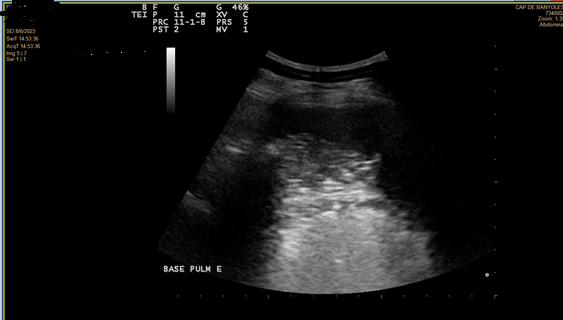

En la ecografía se objetiva irregularidad en la línea pleural, líneas B coalescentes (light beam) y un patrón de consolidación pulmonar en ambas bases pulmonares (I > D).